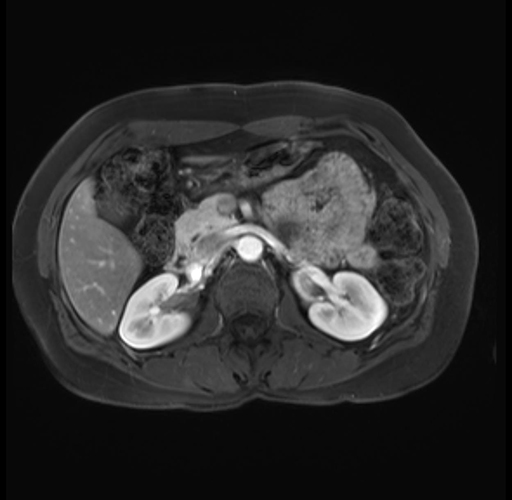

Imaging Analysis

Look through the patient's CT scan to identify any areas of concern for the necessary procedure.

Based on your CT findings, which issue(s) are present and would give reason for "planned slowing down moment(s)" in this case?

Considering a standard distal pancreatectomy procedure, what step(s) of the operation would you do differently in this case?